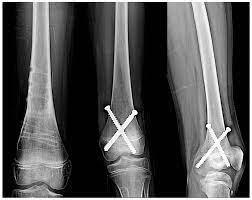

WHAT IS A FRACTURE?A fracture is a partial or complete break in the bone. When a fracture occurs, it is classified as either open or closed:Open fracture (also called compound fracture). The bone exits and is visible through the skin, or a deep wound that exposes the bone through the skin.Closed fracture (also called simple fracture). The bone is broken, but the skin is intact.Fractures have a variety of names. Below is a listing of the common types that may occur in children:Greenstick: Incomplete fracture. A portion of the bone is broken, causing the other side to bend.Transverse: The break is in a straight line across the bone.Spiral: The break spirals around the bone; common in a twisting injury.Oblique: Diagonal break across the bone.WHAT CAUSES A FRACTURE?Fractures occur when there is more force applied to the bone than the bone can absorb. Bones are weakest when they are twisted.Breaks in bones can occur from falls, trauma, or as a result of a direct blow or kick to the body.A child’s bone differs from adult bone in a variety of ways:A child’s bone heals much faster than an adult’s bone. The younger the child, the faster the healing occurs.Bones are softer in children and tend to buckle or bend rather than completely break.Children have open growth plates, also called epiphysis, located at the end of the long bones. This is an area where the bone grows. Injury to the growth plate can lead to limb length discrepancies or angular deformities.TREATMENT FOR A FRACTURE:Specific treatment for a fracture will be determined by your child’s doctor based onYour child’s age, overall health, and medical historyExtent of the fractureYour child’s tolerance for specific medications, procedures, or therapiesExpectations for the course of the fractureYour opinion or preferenceThe goal of treatment is to control the pain, promote healing, prevent complications, and restore normal use of the fractured area.An open fracture (one in which the bone exits and is visible through the skin, or where a deep wound exposes the bone through the skin) is considered an emergency. Seek immediate medical attention for this type of fracture by calling 911.Treatment may include:Splint or cast. This immobilizes the injured area to promote bone alignment and healing to protect the injured area from motion or use.Medication (for pain control)Traction. Traction is the application of a force to stretch certain parts of the body in a specific direction. Traction consists or pulleys, strings, weights, and a metal frame attached over or on the bed. The purpose of traction is to stretch the muscles and tendons around the broken bone to allow the bone ends to align and heal.Surgery. This may be required to put certain types of broken bones back into place. Occasionally, internal fixation (metal rods or pins located inside the bone) or external fixation devices (metal rods or pins located outside of the body) are used to hold the bone fragments in place to allow alignment and healing.